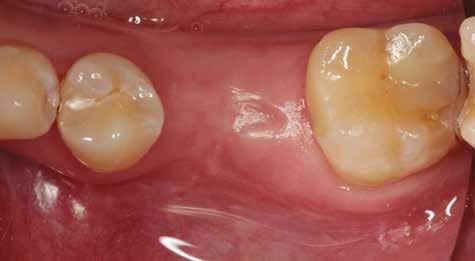

A fogpótlás készítésének lépései

Hathetes gyógyulás után a lágyszövetek kiválóan gyógyultak, és minden implantátum megfelelően osszeointegrálódott, amelyet a radiológiai vizsgálat is megerősítetett (9. és 10. ábra).

10. ábra: Lágyszövetek a hat hét gyógyulást követően.

11. ábra: Az elkészült híd a szájban – okkluzális nézet.